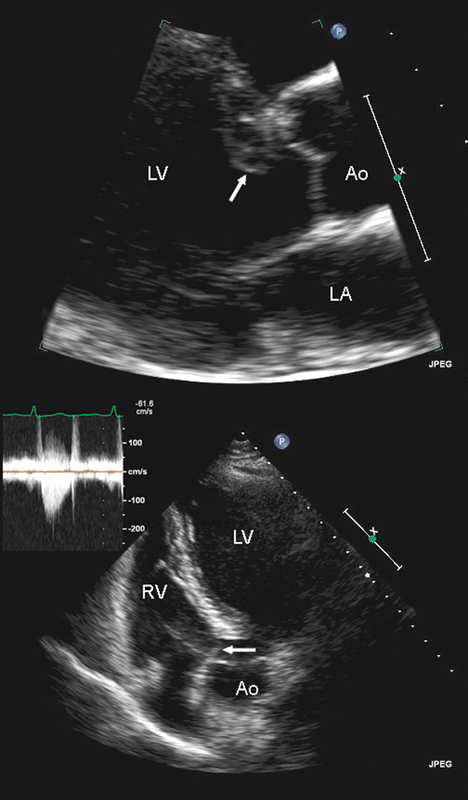

فحوصات تشخيصية لبعض امراض القلب والشرايين التاجية